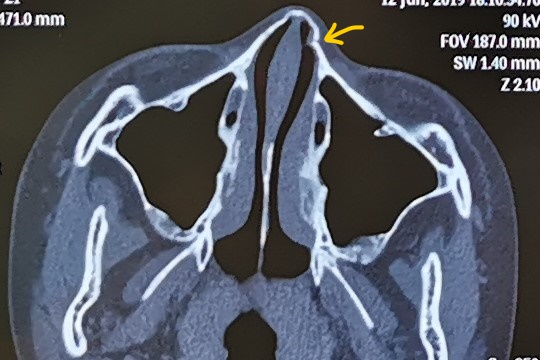

Ct画像あり 鼻骨骨折の判断は 何科を受診 症状 治療は

鼻骨骨折は、治療が必要なことがあります。 鼻骨は鼻を形づくる骨で、骨折している場合は外から見ても鼻の形が曲がって見えます。 まず、正面から見て、鼻筋が曲がっていないか? 次に、横から見て、凹んでいないか? を見ます。 もし明らかに異常であれば、鼻のレントゲンやCTが撮影外来受診される方へ 何科で診てもらう? 小児科は中学生までのこどもの内科疾患です。 外傷や眼科・皮膚科・耳鼻科疾患等は各診療科をご受診ください。 こちらのページは、受診等される際のご参考にお使いください。 ご不明な場合は、内科・総合鼻骨骨折をしたら、何科の病院に行けばいいの? こんにちは! ご説明させていただきます。 何科に行けばいいのか迷われます。 実は、鼻骨骨折の種類によって行く科が変わってきます! 整形外科では骨折してしまった鼻の治療は行いません。 首、足